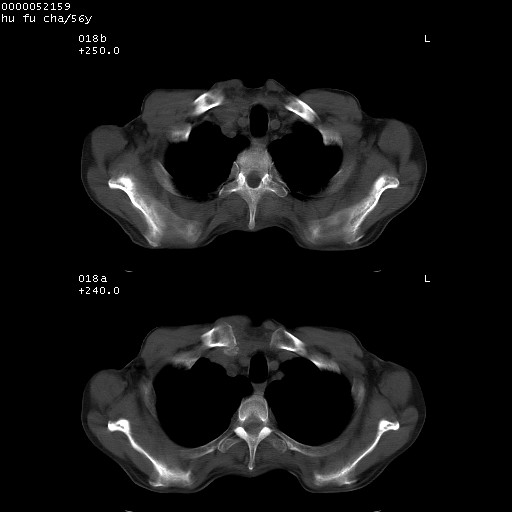

以下是引用zsl6918在2008-8-25 22:47:00的发言:[br]胸骨,胸椎及肋骨均可见多发转移表现,肝内低密度结节不除外转移。原发灶可能在右肺。双侧可见支扩表现。

以下是引用宇宙ct在2008-8-25 23:26:00的发言:[br][br] 胸骨,胸椎及肋骨均可见多发转移表现,肝内低密度结节不除外转移。原发灶可能在右肺。双侧可见支扩表现。 [br] [br]

以下是引用卜一在2008-8-26 8:02:00的发言:[br][br] 支持:肺癌并肺内,胸骨,胁骨,胸椎及肝内转移!另:左肺支气管扩张征伴感染! [br]

以下是引用zjzjr在2008-8-26 11:03:00的发言:[br]支持:肺癌并肺内,胸骨,胁骨,胸椎及肝内转移!另:左肺支气管扩张征伴感染!